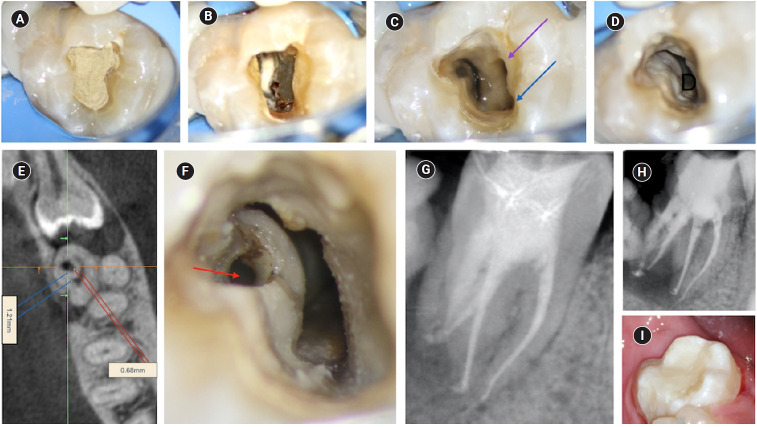

本病例报告描述了三根下颌第二磨牙的III型B齿内陷(DI)的根管治疗,因为内陷侵入根并延伸到根尖。下颌第二磨牙的临床和锥形束计算机断层检查显示冠状形态变宽,DI,第三根,根尖周放射率,内陷压迫远端根管,形成非典型的半月形。诊断为牙髓坏死,有症状的根尖和牙周炎。因此,进行三维虚拟重建,以改善解剖解释和病例规划,并通过减少操作员压力和最小化术中变量来加快术中阶段。本病例报告旨在提高人们对下颌第二磨牙DI存在的认识。

The present case report describes the endodontic treatment of a type III B dens invaginatus (DI) in a three-rooted mandibular second molar since the invagination invades the root and extends apically. Clinical and cone-beam computed tomography examination of the mandibular second molar showed a broadened coronal morphology, DI, a third root, periapical radiolucency, and compression of a distal root canal by the invagination, which developed an atypical semilunar shape. The tooth was diagnosed with pulpal necrosis, symptomatic apical, and peri-invagination periodontitis. Consequently, three-dimensional virtual reconstruction was conducted to improve anatomical interpretation and case planning and accelerate the intraoperative phase by reducing operator stress and minimizing intraoperative variables. The present case report aims to raise awareness of the existence of DI on the mandibular second molar.